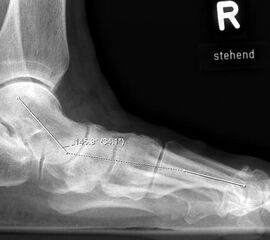

Der Talo-Metatarsale I Winkel bzw. die laterale talonaviculare Subluxation auf der stehenden dorsoplantaren Aufnahme des Fuβes dokumentieren das Ausmaβ des Vorfuβ abductus (Abb. 6 a,b). Ein dp Talo-Metatarsale I Winkel von > 10° (nach medial konvex) ist als pathologisch anzusehen. Mit der Bestimmung der talocalcanearen Divergenz (Abb. 6 c) erhält man ein Eindruck über das Ausmaβ des Rückfuβ valgus; eine leichte Divergenz bis ca. 12° gilt als physiologisch 20.

Auf der seitlichen, stehenden Aufnahme des Fußes wird ebenfalls der laterale Talo-Metatarsale I Winkel (Abb. 6 d) gemessen und so das kollabierte mediale Längsgewölbe dokumentiert. Auch hier gilt ein Talo-Metatarsale I Winkel von > 5° (nach plantar konvex) als pathologisch 21. Der Kollaps findet dabei meist im Talonaviculargelenk, seltener in der Naviculocuneiform-Gelenkreihe statt. Instabilität und Arthrose im 1. TMT sollten ausgeschlossen oder bei der Operationsplanung mit einbezogen werden. Weitere wichtige radiologische Messungen zur Beurteilung der Planovalgus-Statik und Progression der Deformität sind der laterale talo-calcaneare Winkel (Abb. 6 e) und der Abstand des Os cuneiforme-Unterrandes zum Untergrund (Abb. 6 f, Cuneiform height, 22. Eine anteriore Translation des Talus auf dem Kalkaneus findet man sowohl auf der ap, als auch auf der seitlichen Aufnahme des Fuβes mit Aufhebung der Cima-Linie.